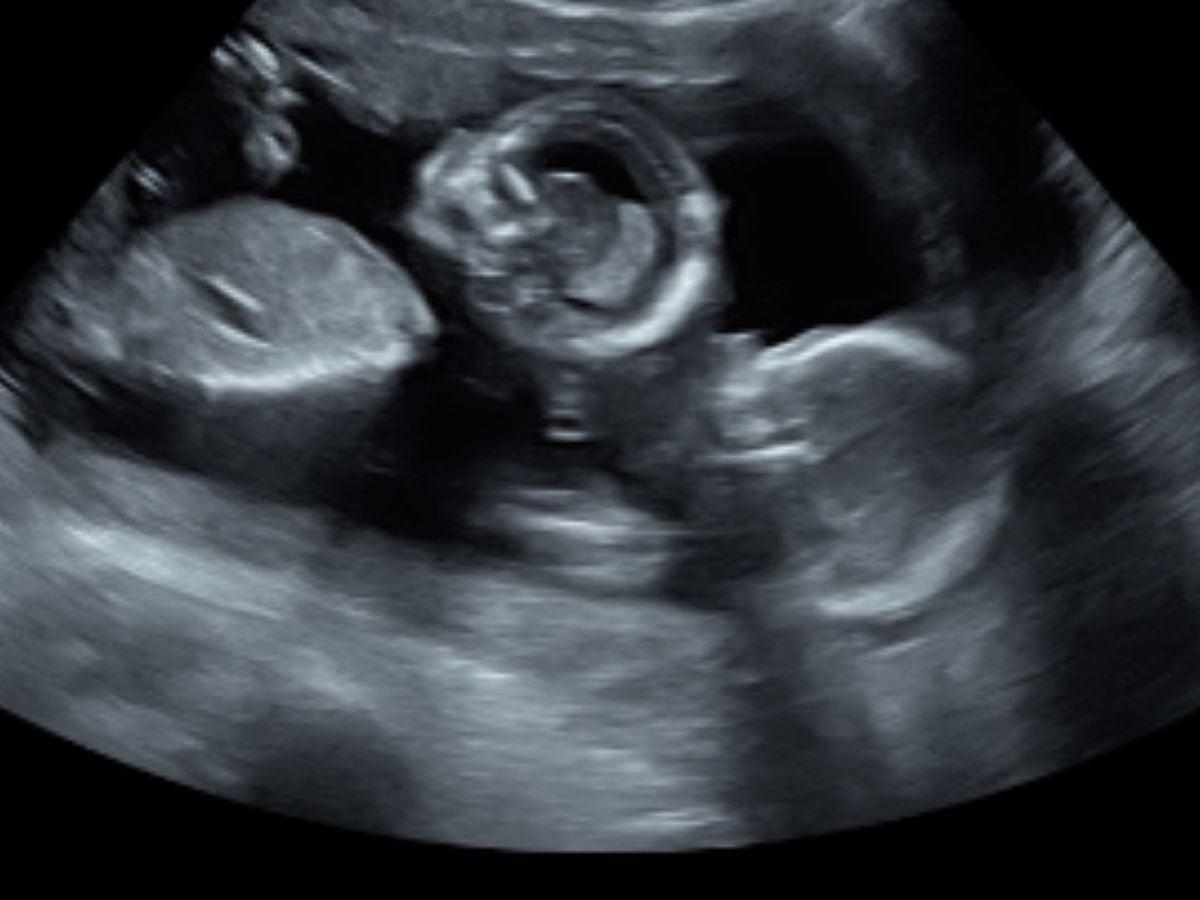

Hello my name is Stephanie Korth! I am doing this go fund me for two of the most selfless people I have ever met, Kyle Meradith and Sarah Hicks. Sarah is 18 weeks pregnant with twin girls. At 16 weeks they started to notice the twins not growing correctly. They call it TTTS (TWIN TO TWIN TRANSFUSION SYNDROME) They have just recently been hit with so many trips back and forth to Denver and Scottsbluff, as well as taking off work for these appts. Things are going to start piling up and I’m hoping that this will put their mind at lease a little.

Twin to Twin Transfusion Syndrome (TTTS) is a prenatal condition in which twins share unequal amounts of the placenta's blood supply resulting in the two fetuses growing at different rates. 70% of identical twins share a placenta, and 15-20% of these pregnancies are affected by TTTS.